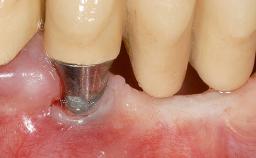

Soft-Tissue Volume Augmentation Using a Connective-Tissue Graft Harvested from the Maxillary Tuberosity

Type of Implants One-Piece

Attachment One-Piece

Soft Tissue Grafting Simultaneous